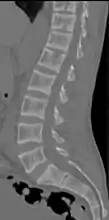

X-ray of a subtle "rugger jersey spine" due to sclerotic bands adjacent to the vertebral endplates.[18]

CT scan of the same case.[18]

Renal osteodystrophy is usually diagnosed after treatment for end-stage kidney disease begins; however the CKD-MBD starts early in the course of CKD.[1][6] In advanced stages, blood tests will indicate decreased calcium and calcitriol (vitamin D) and increased phosphate, and parathyroid hormone levels. In earlier stages, serum calcium, phosphate levels are normal at the expense of high parathyroid hormone and fibroblast growth factor-23 levels. X-rays will also show bone features of renal osteodystrophy (subperiostic bone resorption, chondrocalcinosis at the knees and pubic symphysis, osteopenia and bone fractures) but may be difficult to differentiate from other conditions. Since the diagnosis of these bone abnormalities cannot be obtained correctly by current clinical, biochemical, and imaging methods (including measurement of bone-mineral density), bone biopsy has been, and still remains, the gold standard analysis for assessing the exact type of renal osteodystrophy.[6][16]